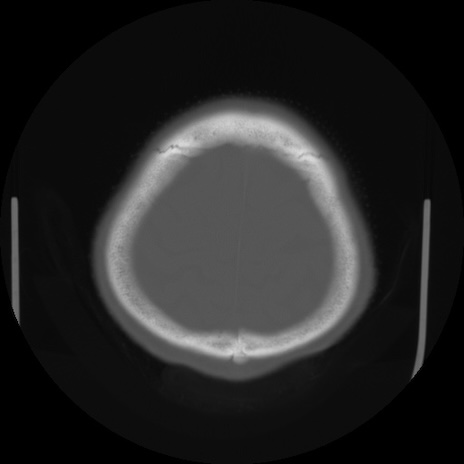

【頭部】症例5 CT(横断像)

【症例】80歳代 男性

【主訴】頭部打撲

【現病歴】外出先で椅子から立ち上がる際に、つまづいて後方へ転倒し受傷。転倒時に意識はあった。

【既往歴】高血圧、不整脈、アルツハイマー病

【身体所見】BP 217/71、HR 96、JCS1-1、 難聴あり、顔色良好、右後頭部に擦過創あり。神経学的異常なし。

症例5の画像所見と診断は?

CT(矢状断像)